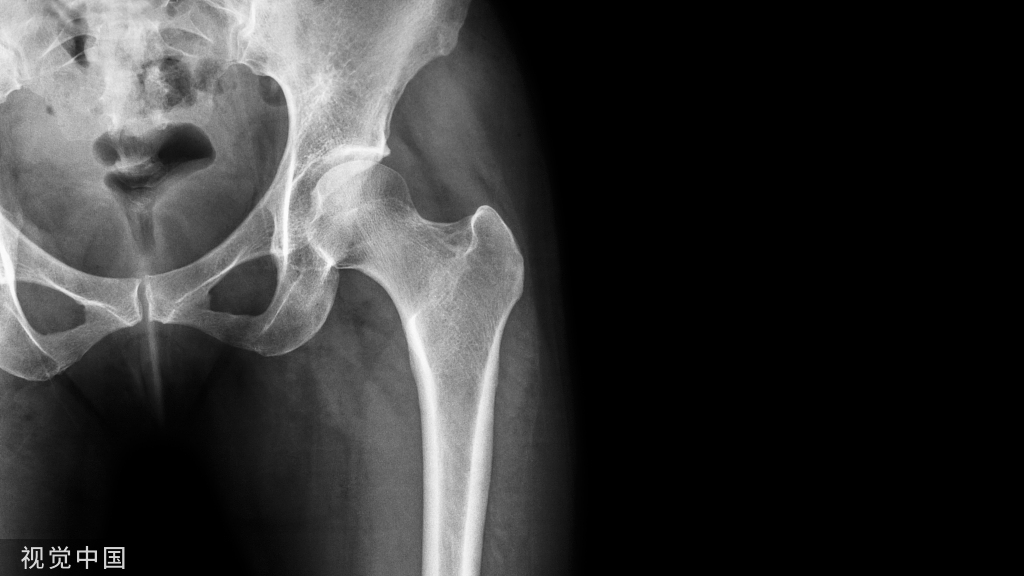

严重粉碎骨折

对于严重粉碎骨折(C3),按照AO理念,首先尽可能间接复位、桥接固定;相对稳定、二期愈合。先打钢板两末端锁定钉,再靠近粉碎骨折区两端各打一枚锁定钉以增加骨折区的稳定性。最后,在稳定螺钉与末端螺钉间视情况再各加打1-2枚锁定钉。仍需注意遵循长钢板、少螺钉的应力分散原则(如下图示)。

粉碎骨折钢板工作距离一般约占钢板总长度的1/3为宜。注:骨折区两锁钉之间的距离为工作距离。